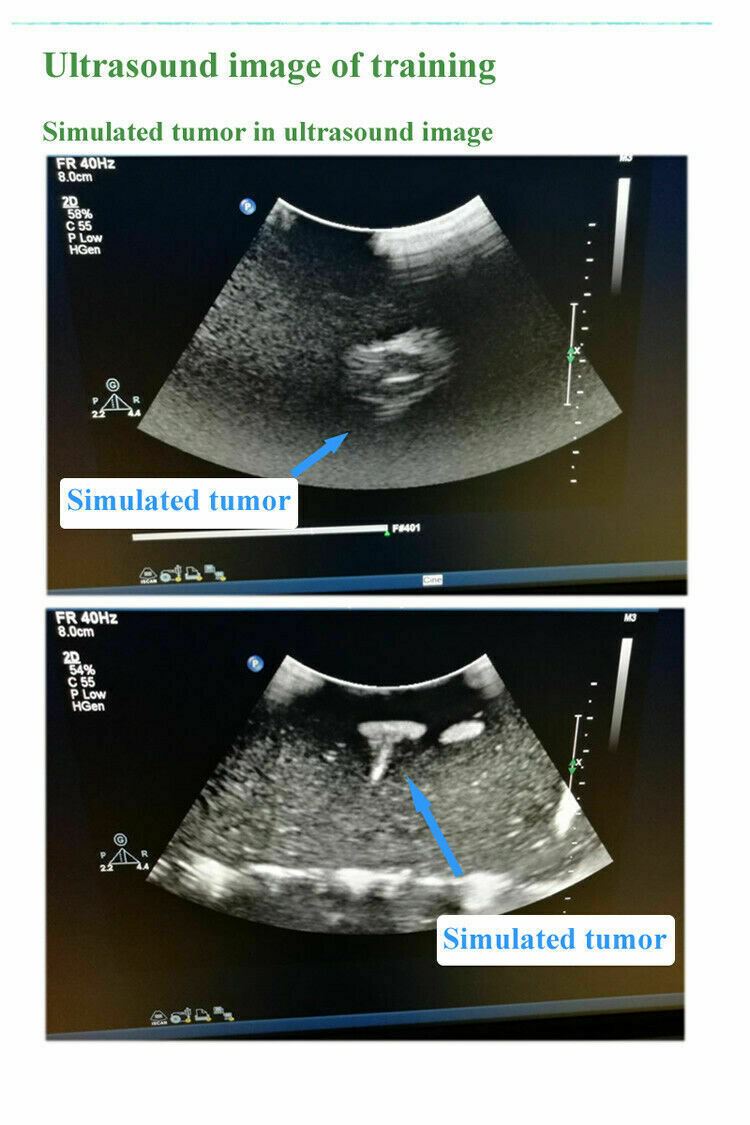

Model for Interventional Ultrasound, Soft tissue, B-Ultrasound Training Teaching

- A training teaching model for interventional Ultrasound

- Several different sized simulated high echo towers with the model